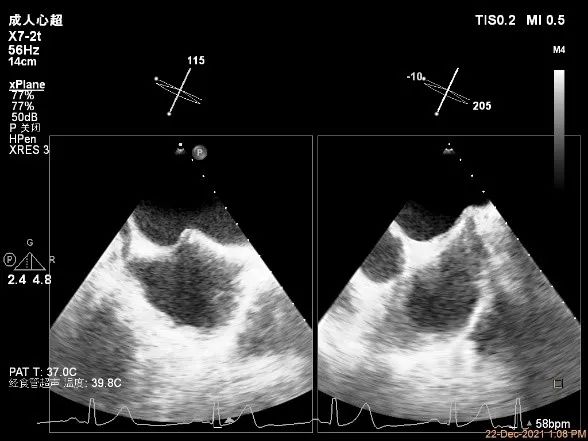

X-plane:下夹子尝试先捕获2区偏内侧瓣叶

夹子关闭过程中,Color提示2区反流逐渐减少,残余反流位于第一个夹子外侧

第一个夹子放置侯二尖瓣口平均跨瓣压差:4mmHg

肺静脉血流频谱恢复正向趋势